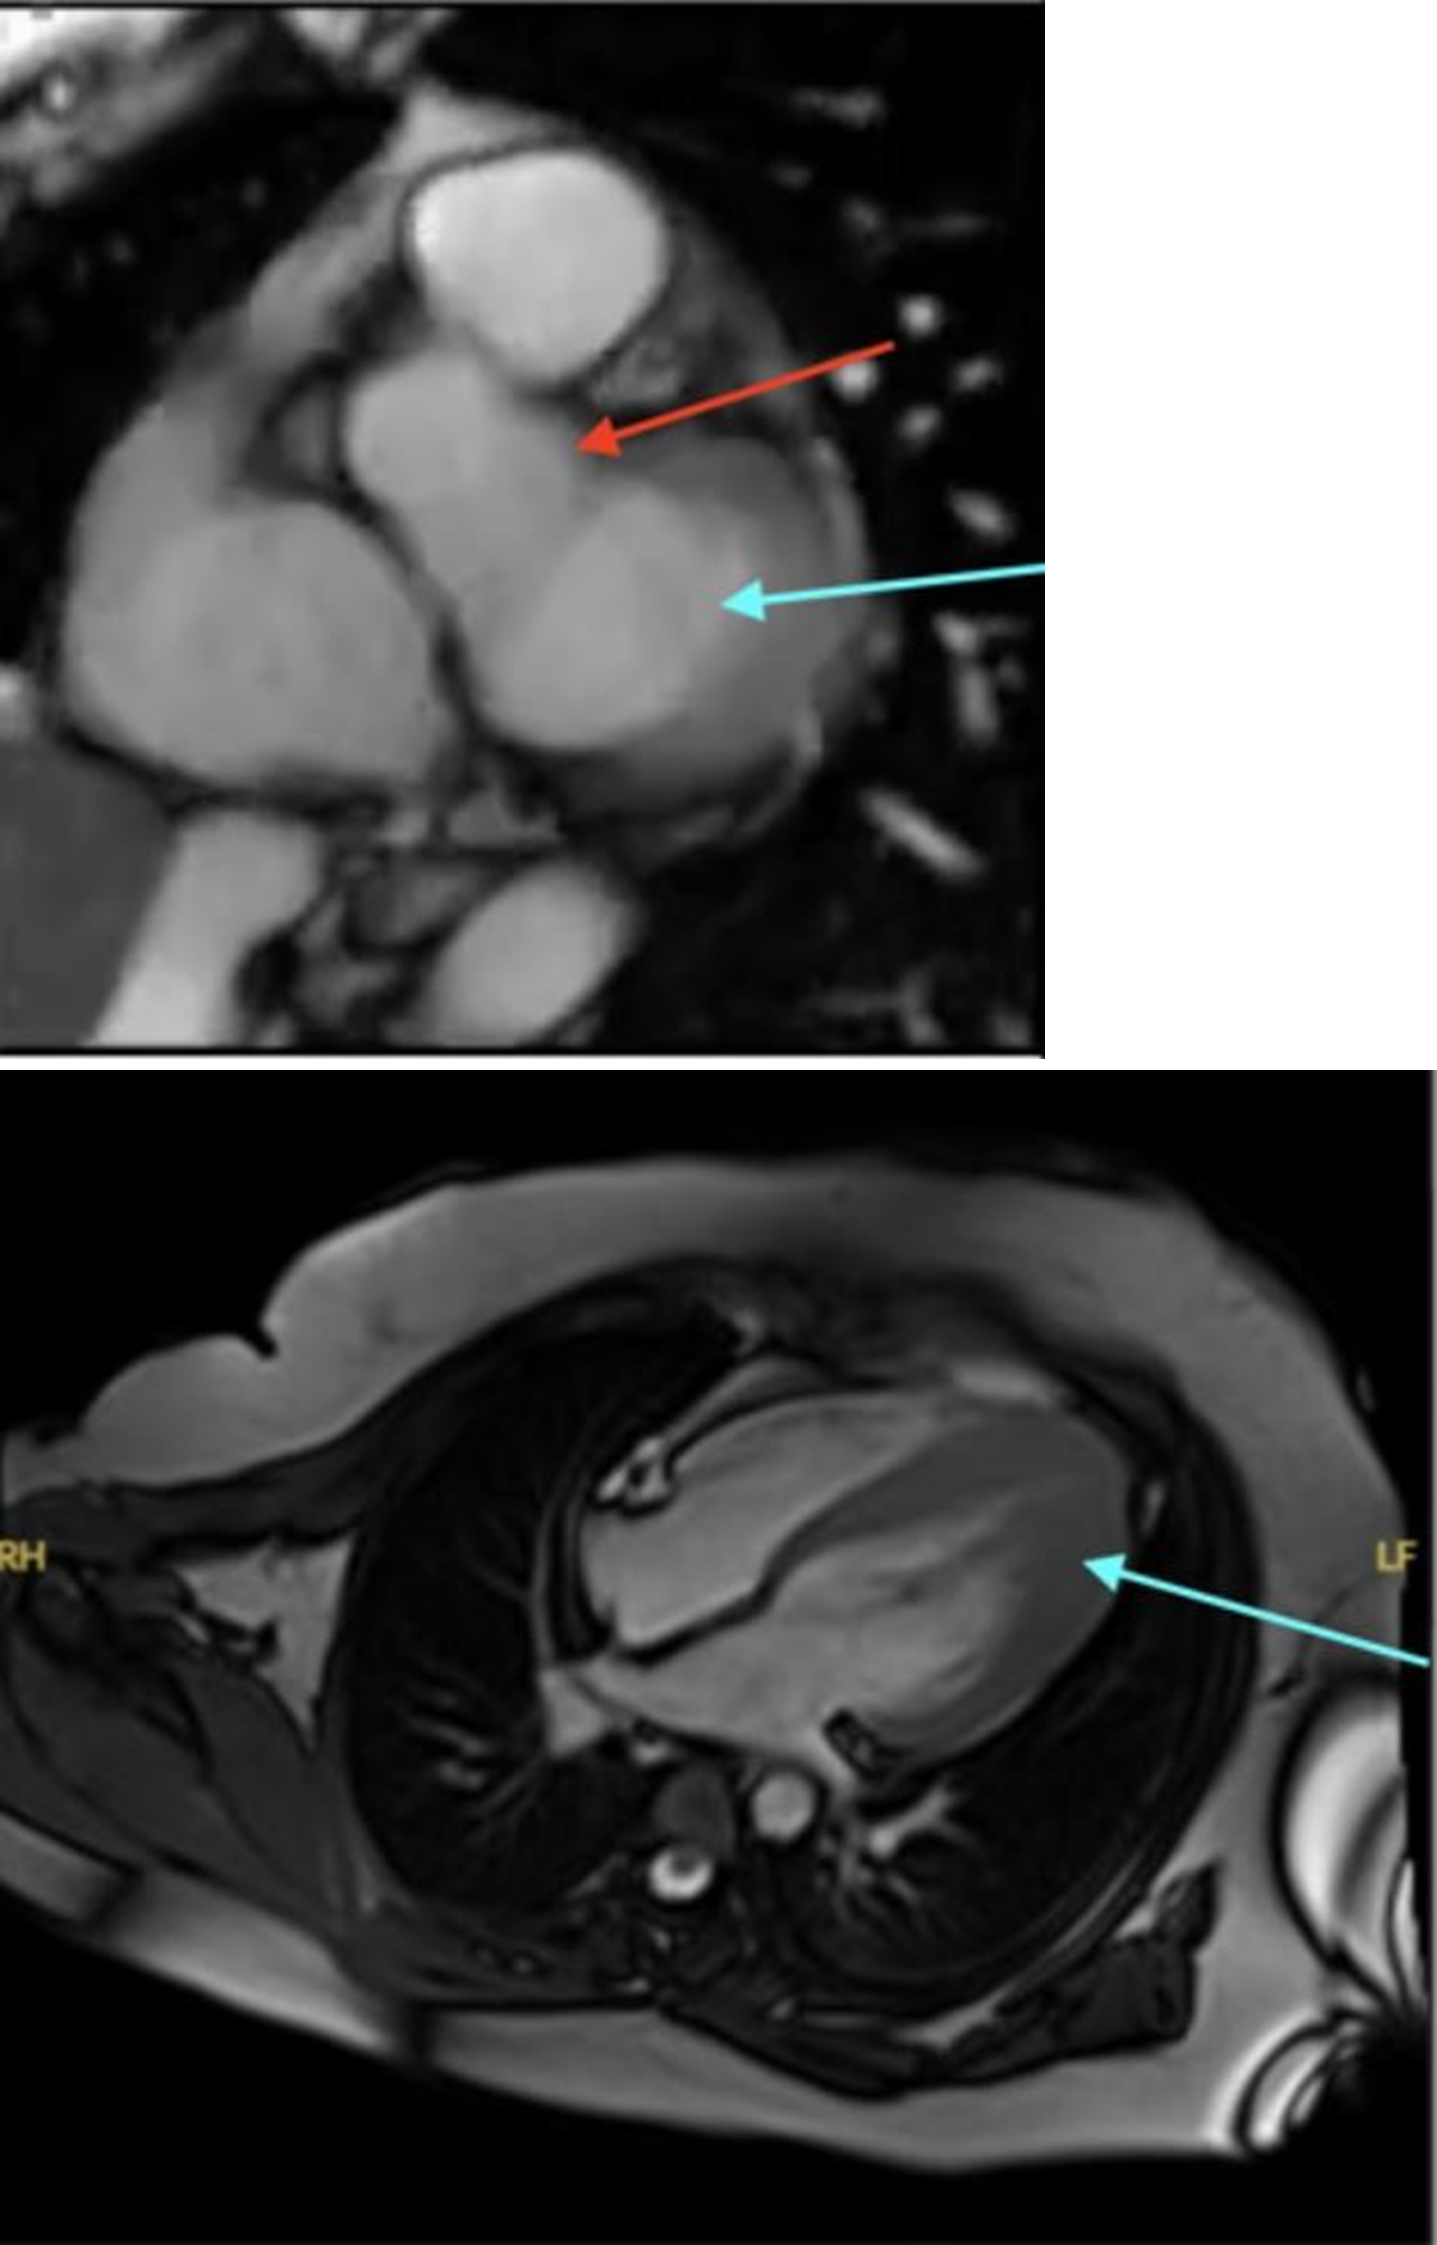

A cardiac MRI with contrast was consistent with the apical variety of hypertrophic cardiomyopathy (Figure 5). The maximum left ventricular wall thickness at the apex was 2.2 cm without evidence of left ventricular aneurysm or wall motion abnormalities. There was also a mild amount of LGE in the mid myocardium in the distal infero-septal/infero-apical regions, suggestive of interstitial fibrosis. A tilt table test to evaluate for vasovagal syncope was performed by cardiac EP, which returned positive. The test reproduced syncope with similar prodrome to prior episodes. As a result, the patient was started on 25 mg metoprolol succinate once daily. ICD placement was deferred in the absence of demonstrable ventricular arrhythmias, and the presence of a cardioinhibitory etiology of her vasovagal syncope. An internal loop recorder (ILR) was implanted for long-term monitoring. Post- discharge, the patient was unable to tolerate metoprolol due to burning sensation and skin discomfort and was switched to nadolol. Unfortunately, this patient had a similar reaction to nadolol in addition to itching of her eyes, and beta blockers as a class were discontinued. EP cardiology determined that she can be monitored off beta blockers at present. Genetic testing detected an autosomal dominant variant of FLNC (filamin C, an actin-binding protein primarily expressed in heart and skeletal muscle) considered to be of unknown clinical significance, for which the patient is heterozygous. Per EP cardiology recommendations, a cardiac MRI will be repeated to assess for apical aneurysm and increased LGE from the prior study, as there are reports of this variant being associated with a higher incidence of SCD [18].

Figure 5. Cardiac MRI. The first image demonstrates a normal cardiac MRI, with no evidence of left ventricular hypertrophy. The blue arrow demarcates the left ventricle and the red arrow identifies the ascending aorta. The normal cardiac MRI listed was not from our patient of the case discussion, rather it was obtained from the Cardiac MRI learning center [19]. The second image was a cardiac MRI of the patient from the case discussion, demonstrating the presence of apical hypertrophic cardiomyopathy as outlined by the blue arrow.